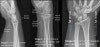

Wrist X-ray에서의 연부조직(Soft tissue) 체크

Soft tissue swelling is almost always seen in one or more compartments in cases of acute fracture or dislocation.

Abnormal fat planes : fat plane is convex out of the underlying bone, or loss of its distinct plane.